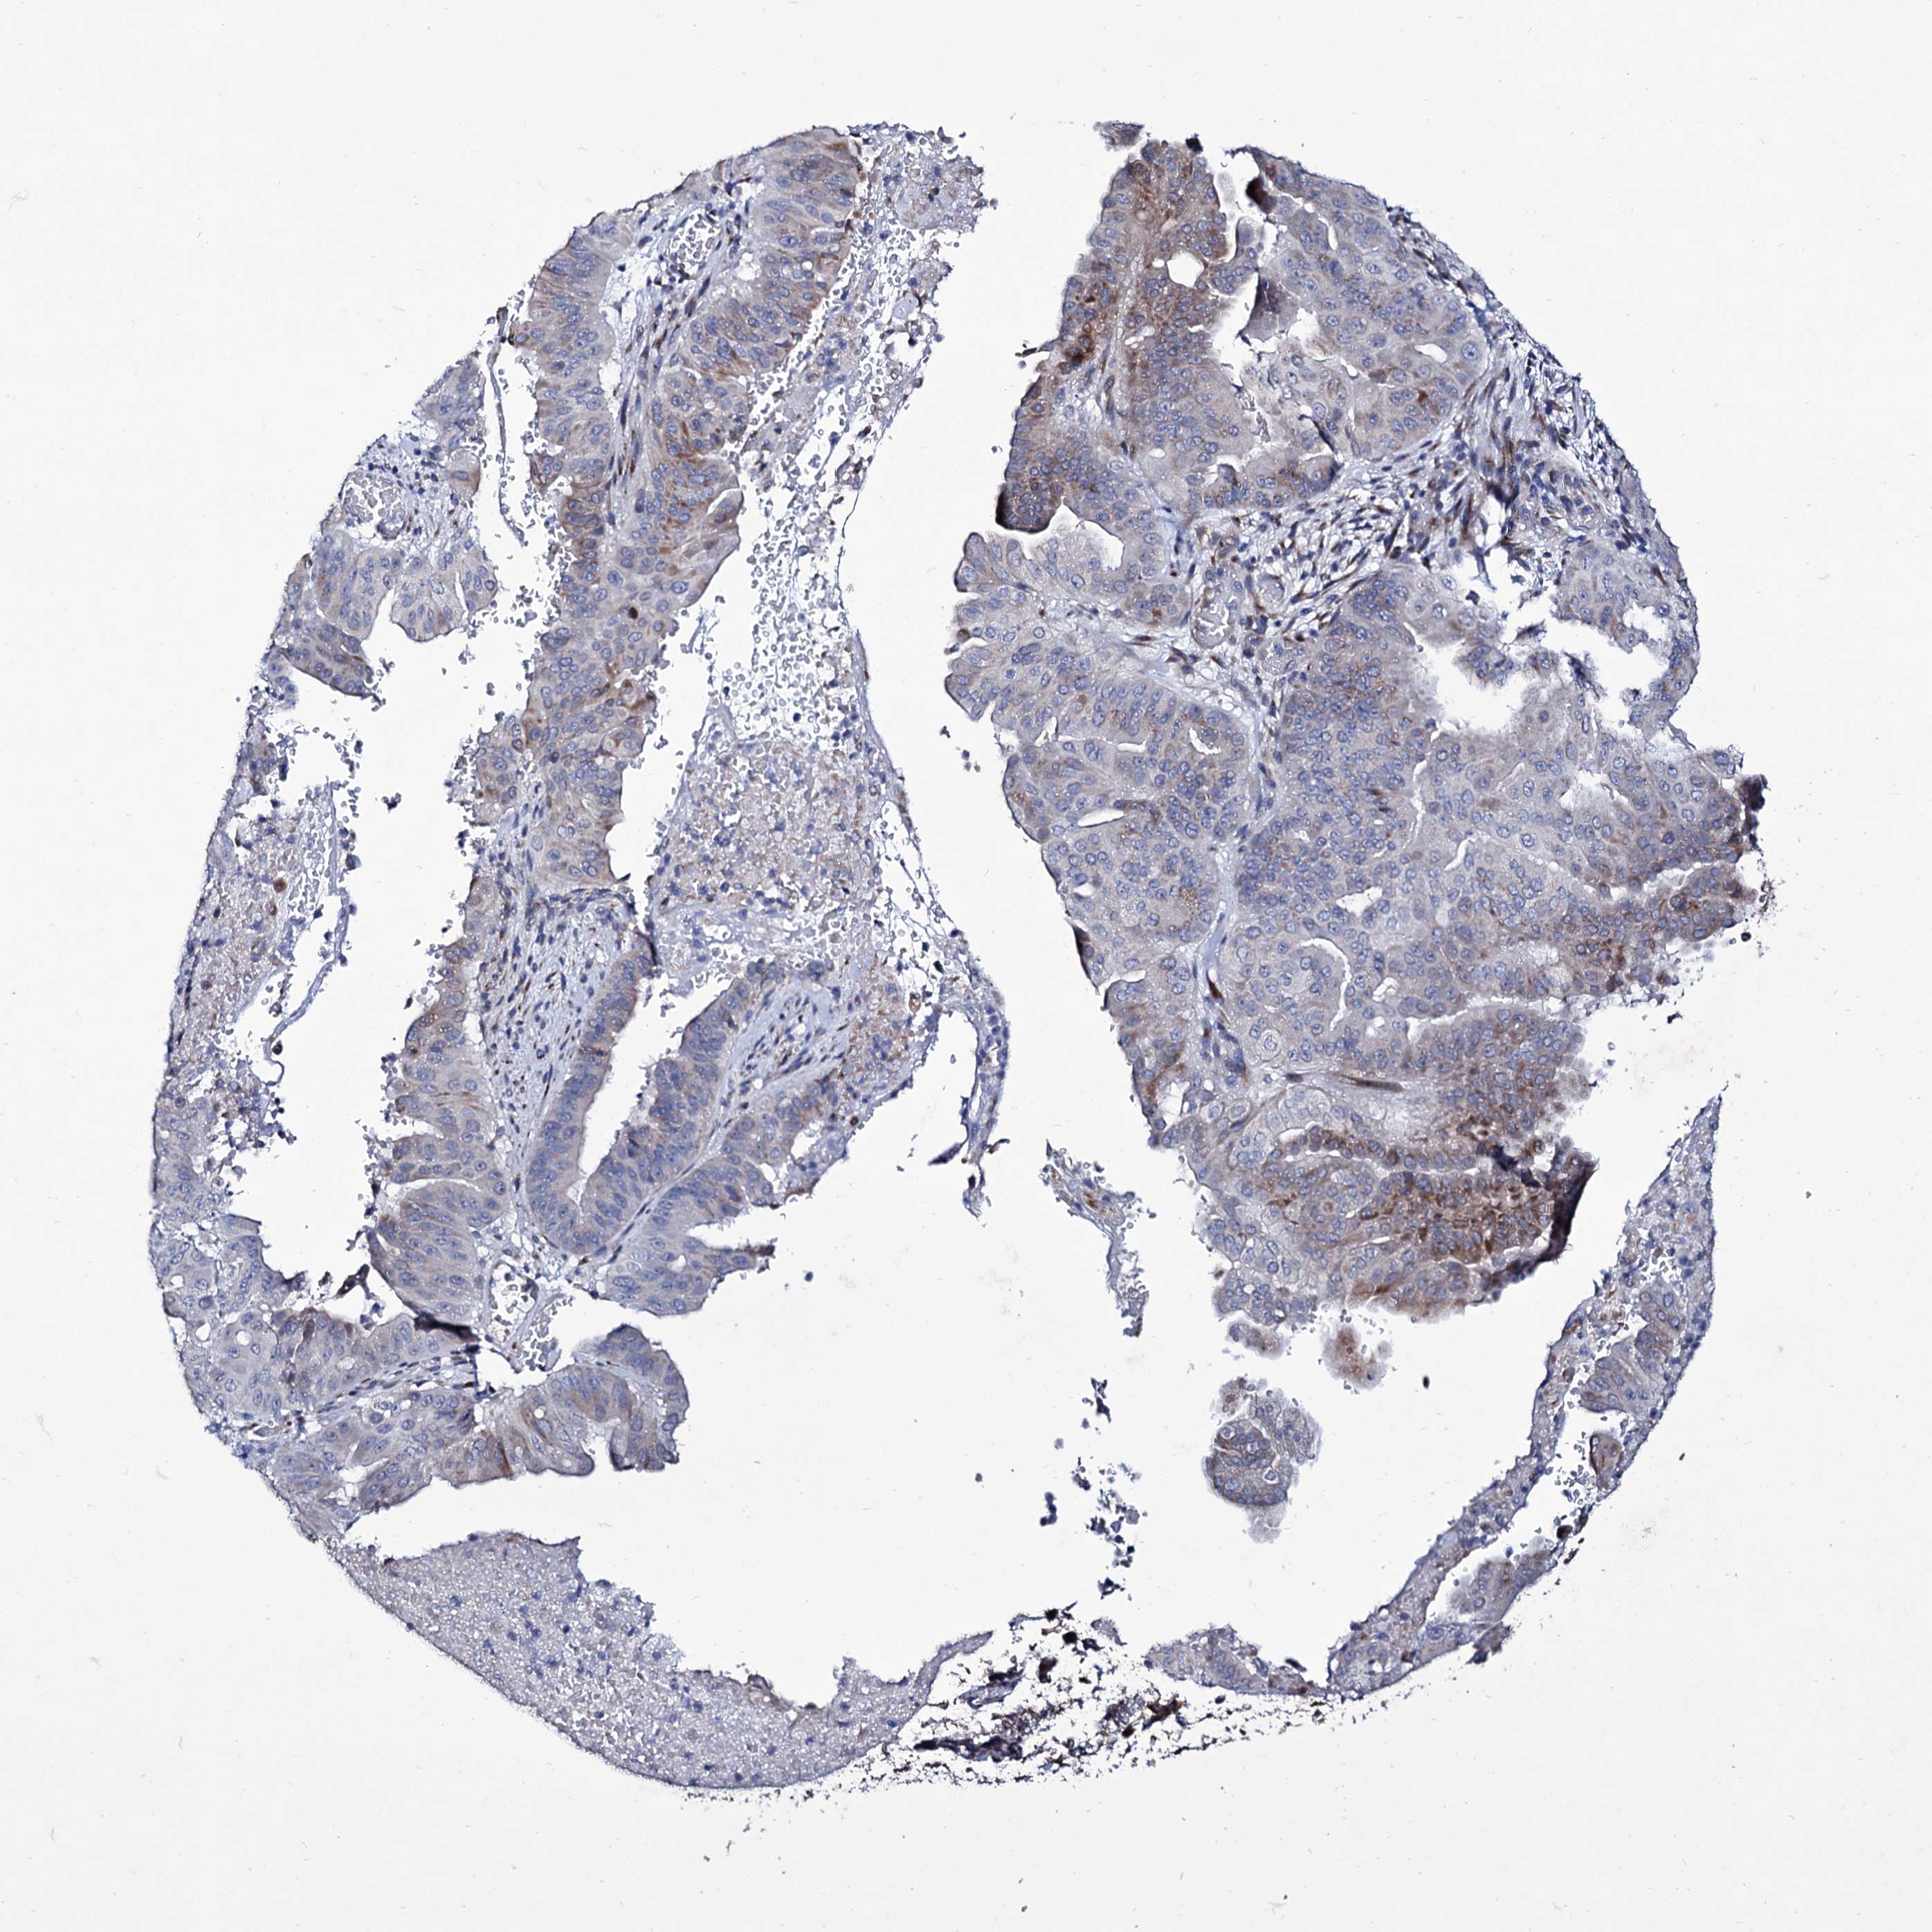

PANCREATIC CANCER - Protein expressioni

A mouse-over function shows sample information and annotation data. Click on an image to view it in a full screen mode. Samples can be filtered based on level of antibody staining by selecting one or several of the following categories: high, medium, low and not detected. The assay and annotation is described here.

Note that samples used for immunohistochemistry by the Human Protein Atlas do not correspond to samples in the TCGA dataset.

Antibody stainingi

Antibody staining in the annotated cell types in the current human tissue is reported as not detected, low, medium, or high, based on conventional immunohistochemistry profiling in selected tissues. This score is based on the combination of the staining intensity and fraction of stained cells.

Each image is clickable and will lead to virtual microscopy that enables deeper exploration of all samples and also displays staining intensity scores, fraction scores and subcellular localization as well as patient and tissue information for each sample.

Antibody HPA039366

Staining

High

Medium

Low

Not detected

Intensity

Strong

Moderate

Weak

Negative

Quantity

>75%

75%-25%

<25%

None

Location

Nuclear

Cytoplasmic/membranous

Cytoplasmic/membranous,nuclear

Adenocarcinoma, NOS